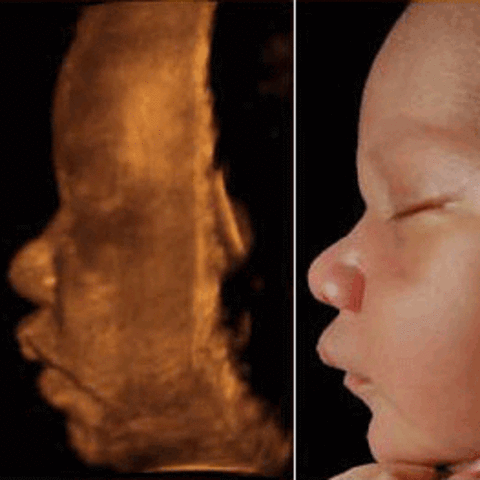

• Development of 3-D

Development of 3-D

3-D ultrasound was developed and 3-D images were captured of a fetus. A 3D ultrasound is acquired by emitting high-frequency sound waves. Researchers in Scotland began working on a multiplanar scanner. As computers developed, a true 3D ultrasound became more feasible. In 1984, the first concrete work on a Japanese 3D ultrasound began, and was successful by 1986. -WiseGeek Reference:

• Development of 4-D (Real Time) / Ultrasound Progression

Development of 4-D (Real Time) / Ultrasound Progression

4-D ultrasound (real time) was developed . Ultrasound guided biopsies were also beginning to develop into everyday practice. Due to the fact that 4D machines create a higher quality image, there is some concern that the energy level used by them may be higher, although this has not been proven. -WG Reference: